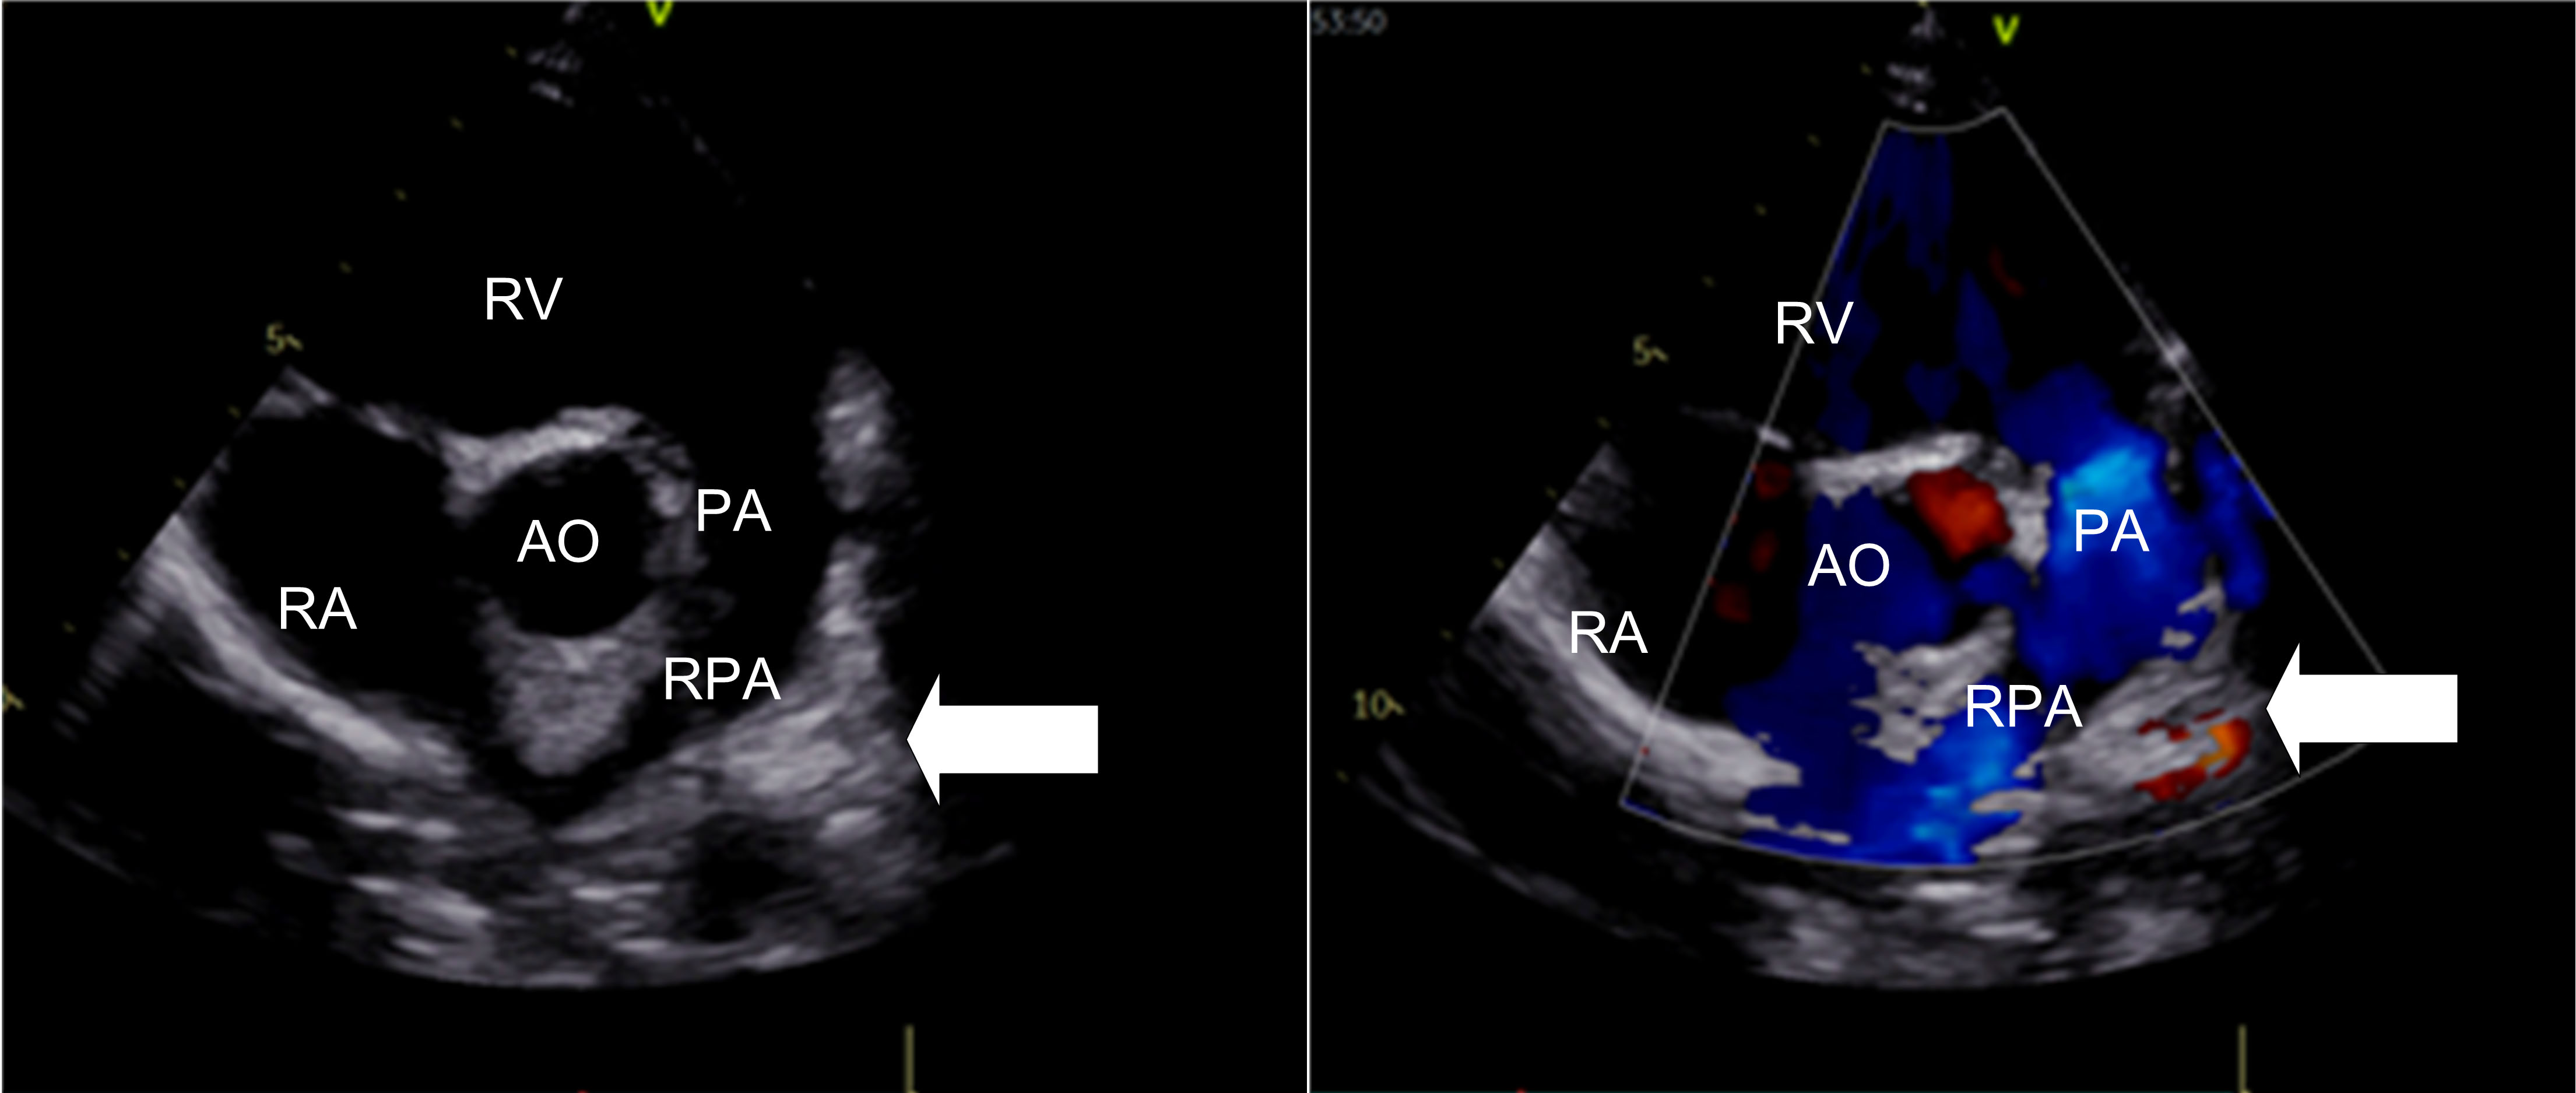

A 3-year-old girl with absent left pulmonary artery complicated with tetralogy of Fallot (TOF) and atrial septal defect (ASD) is shown in Fig. 4 (stenosis group). This three-year-old girl had found out the absence of the left pulmonary artery combined with tetralogy of Fallot and atrial septal defect by echocardiography before congenital heart surgery. Intraoperative findings comfirmed there was no left pulmonary artery emission from the main pulmonary artery. The girl accepted radical correction operation of TOF and the repair of ASD, the pulmonary artery was not treated, echocardiographic postoperative follow-up only.

Fig. 4.Short axis view of great vessels (Color Doppler and 2D image). In this view there is not left pulmonary artery structure from the main pulmonary artery (arrow). PA, main pulmonary artery; LPA, left pulmonary artery; AO, Aorta; RV, right ventricle; RA, right atrium.

In addition, the reasons of ultrasound misdiagnosis in UAPA is mainly due to insufficient caution of this disease during scanning. This may be due to insufficient understanding of the disease or the patient’s image is unclear due to lung disease. If it was found that the pulmonary artery was not clearly displayed in the examination, cardiologists or sonographers should pay attention to scanning the high level short-axis view of the great vessels. Use color Doppler to detect pulmonary artery branch and the situation of the left and right pulmonary artery. According our experience, there were two situation were most easily misdiagnosed: (1) For the left pulmonary artery absence patient, the ductus arteriosus is often misdiagnosed as a pulmonary artery branch (Fig. 1). This may be due to insufficient knowledge of the disease or the operating doctor’s inadequate scanning of the branches of the pulmonary artery. (2) Tetralogy of Fallot (TOF) patients combined with the absence of pulmonary arteries are easily missed also (Fig. 4), the misdiagnosis rate was as high as 77% (7/9), the reason was considered as following: TOF patient’s pulmonary artery branches were usually very thin, which were difficult to detect by 2D echocardiography, and pulmonary stenosis induced blood flow turbulence, which affected pulmonary branch color Doppler imaging.